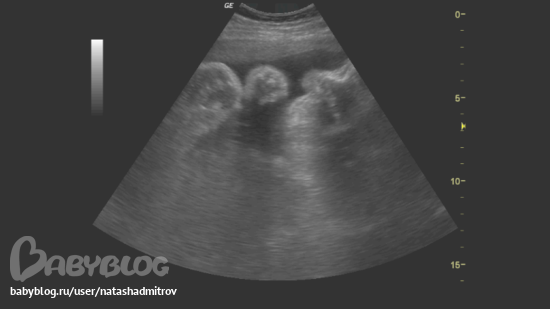

а вот И НАШЕ СОЛНЫШКО:

и наши щечки )))))